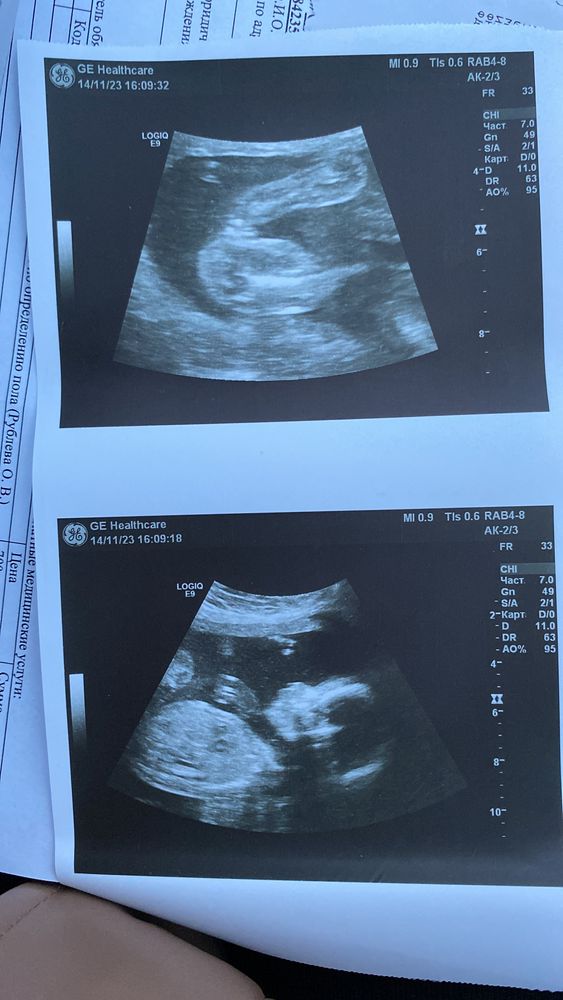

Определение Пола по фото узи

Мальчик мне кажется

Галина, что-то как-то размыто.... Я вот в 14 недель увидела и срущу поняла что девочка. Моя не стеснялась села так что всё было видно. Но вроде мальчик... Вообще рано говорить об этом ведь ещё органы половые не до конца сформировались.... Вот у меня с сыном только на 23 недели смогли сказать кто точно, а с дочкой уже в 11 недель сказали что девочка. Главное чтобы был самый счастливый и здоровый. Лёгких родов и здоровья вам)

Галина, ну я смотрю похожа на девочку, но слишком длинный наверное пальчик... У меня вообще подружка ходила и всё говорили девочка а родила мальчика, хорошо что сама родила и показали что мальчик а то не поверила бы. Размеры разные бывают поэтому.... Мне кажется мальчик просто неверное только всё начало формировать. А вообще прислушайтесь к себе. Ведь мы же в глубине души знаем кто. Я вот 1Б хотела девочка и говорила что девочка наверное, но что-то внутри мне говорил что мальчик и в 2Б думала мальчик всё так думали, но я чувствовала что девочка. Главное услышать этот голос) А вообще конечно не понятно кто... Но пальчики на ножке хорошо видно, такие сладкие) ой, как я скучаю по животику ( хотя только 4 месяца прошло.... Хотя я ходила с 1б- 42 недели 2б- 43 недели..... Долго его мне хотелось ещё как можно дольше ходить!

Камилла , мне кажется вот половые губы, сейчас только увеличила и увидела. Видно половые губы и посередине разделение, ну то есть если была бы машонка, то было бы полноценно круглое, а тут прям разделение, ну это я так вижу, а там не знаю🤔 У нас просто пол ребенка бесплатно никто не говорит, принести фотку и попросить посмотреть я не смогу, нужно платить🤦🏼‍♀️ Изображение

На фото нижнем у ребенка вообще не вошло в кадр то место, по которому опрелеляют пол. А верхнее фото... Я не поняла, какая это часть тела...